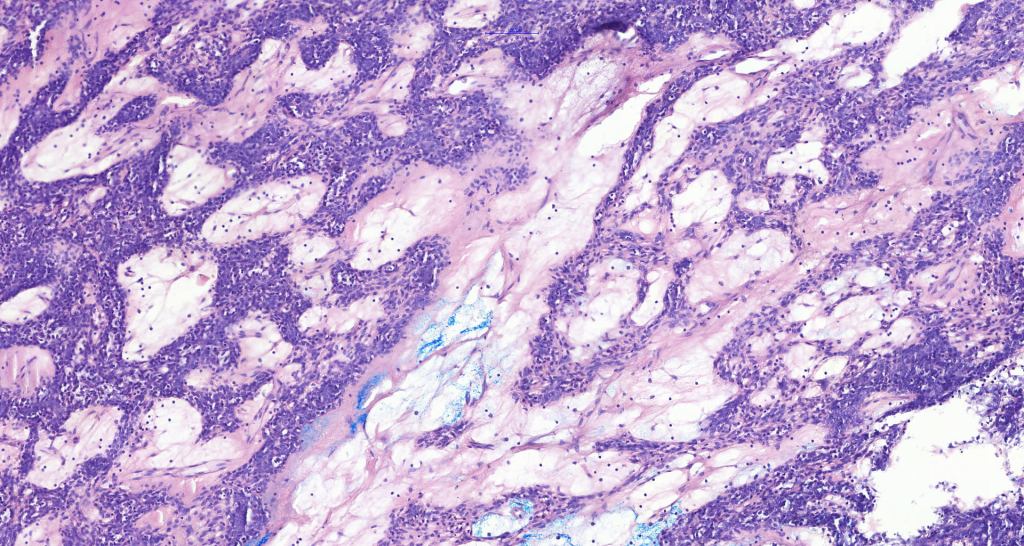

Histological features

•Nodule/multiple blue encapsulated nodules in the dermis +/- subcutaneous fat

•Common association with an adjacent nerve & exceptional intraneural component

•Outer layer of small intensely basophilic cells surrounding larger pale staining or eosinophilic cells with vesicular nuclei & small nucleoli

•Marked lymphedema sometimes present- lymphangiectatic variant

•Spiradenocylindroma

•Association with trichoepithelioma & trichoblastoma